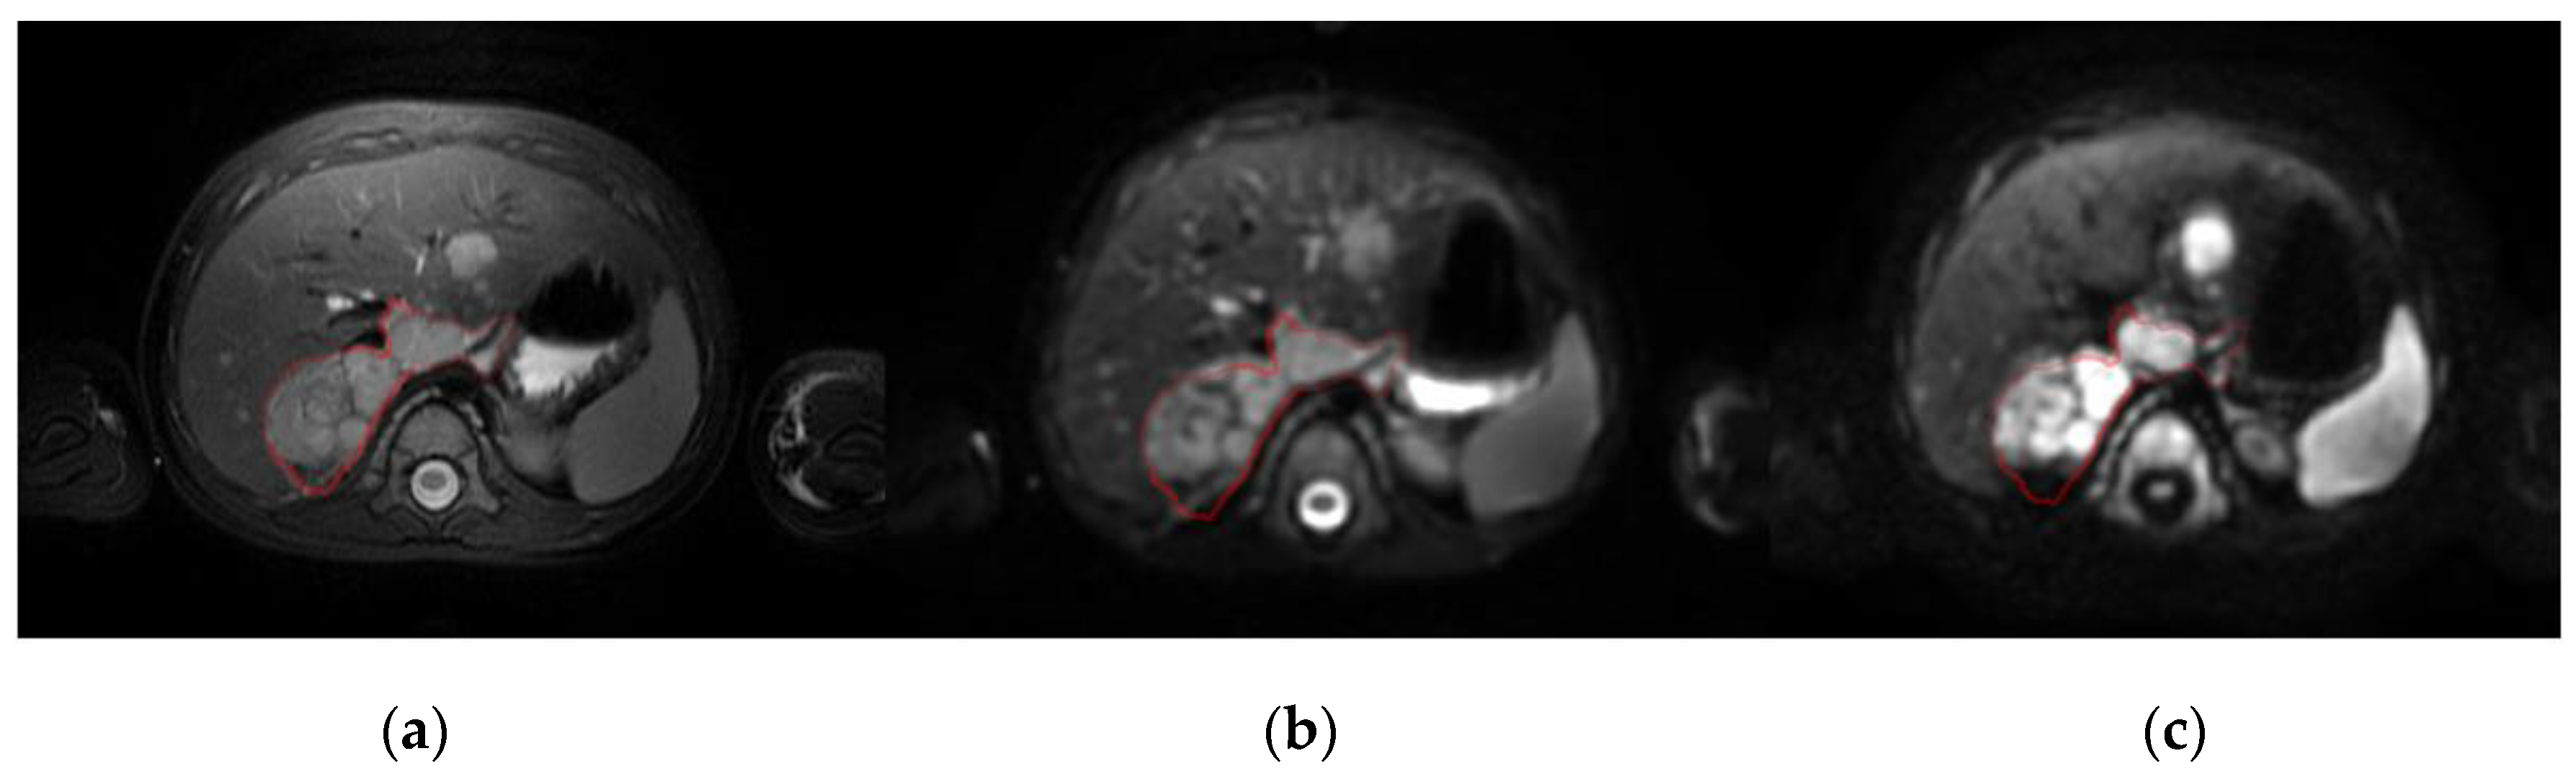

Figure 1.

Baseline MRI of a patient with neuroblastoma in the right adrenal gland and liver metastasis shown on: (a), a T2-weighted image; (b), a DW image with b = 0 s/mm2; and (c), a DW image with b = 800 s/mm2 (right). The red line defines the primary tumor.